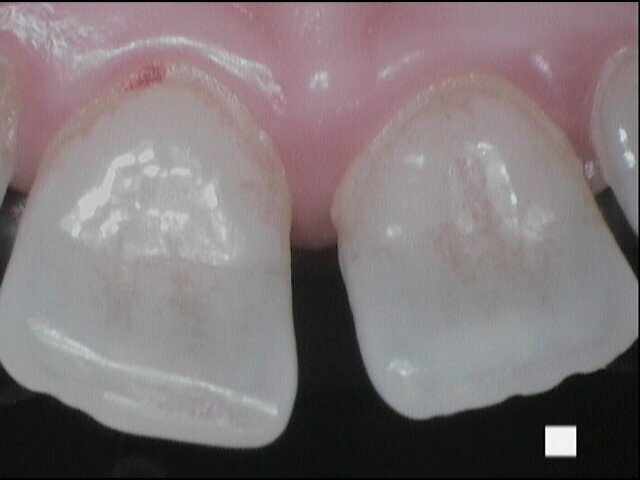

Si presenta alla nostra attenzione un giovane paziente di anni 26, non fumatore, in apparente salute sistemica, in terapia ortodontica con mascherina invisibile lamentando un cattivo odore dell’allineatore, percepito in maniera fastidiosa grazie all’utilizzo obbligato della mascherina per le norme di sicurezza anti-Covid 19. Invitiamo il paziente a rimuovere le mascherine al fine di eseguire un esame obiettivo intra-orale e valutare le condizioni di integrità degli allineatori.

Il paziente ha un buon controllo del biofilm batterico. Viene consigliato il controllo dell’alito attraverso il test organolettico sniff test e il paziente si rassicura poiché non avverte cattivo odore. Chiediamo al paziente in che modo igienizza invece il dispositivo ortodontico e ricordiamo al paziente di aver consigliato l’utilizzo della compressa igienizzante. Il paziente ci riferisce di non aver usato la pastiglia poiché divide l’abitazione con suoi colleghi universitari e non ha piacere di immergere il dispositivo in un bicchiere d’acqua con l’aggiunta della pastiglia igienizzante, poiché lo trova sconveniente e se ne vergogna. Il paziente chiede se può disinfettarla facendola bollire (Figg. 1-9).